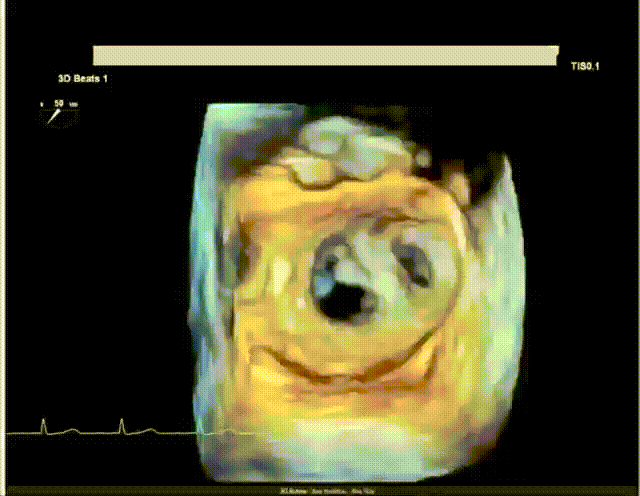

此次手术演示的患者是一名79岁老年女性,既往曾行永久起搏器置入术,合并高血压病、慢性肾脏病等,超声心动图提示“二尖瓣重度反流,A3区脱垂。外科手术高危,STS评分9.71%。

TEE外科视角见偏心反流

术前,王建安教授团队经过充分评估后选用DragonFly器械,术中在超声引导下建立右侧股静脉入路、精准穿刺房间隔,之后继续在经食道超声引导下将瓣膜夹器械输送到左心房,再利用多视角评估瓣膜夹位置和夹合效果。

超声评估少量反流,无残余脱垂,平均跨瓣压差2mmHg。经在场专家讨论后,决定释放二尖瓣瓣膜夹。

最终超声评估显示二尖瓣少量残余反流,二尖瓣平均跨瓣压差2mmHg。患者情况良好,手术顺利完成。